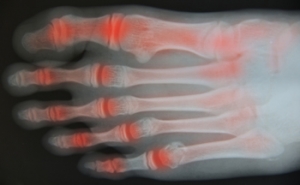

In order to diagnose your bunion, your podiatrist may ask about your medical history, symptoms, and general health. Your doctor might also order an x-ray to take a closer look at your feet. Nonsurgical treatment options include orthotics, padding, icing, changes in footwear, and medication. If nonsurgical treatments don’t alleviate your bunion pain, surgery may be necessary.

A podiatrist knowledgeable in foot structure and biomechanics will be able to quickly diagnose bunions. Bunions must be distinguished from gout or arthritic conditions, so blood tests may be necessary. The podiatrist may order a radiological exam to provide an image of the bone structure. If the x-ray demonstrates an enlargement of the joint near the base of the toe and a shifting toward the smaller toes, this is indicative of a bunion.

Signs of Rheumatoid Arthritis

Many people begin to develop rheumatoid arthritis, or RA, when they reach their 30s or 40s. This disease is an autoimmune disorder in which the body’s immune system actually attacks the body's own tissues. This can cause pain in the joints, including those of the ankles, feet, and toes. Early symptoms of rheumatoid arthritis include fatigue, stiffness, and inflammation in the joints. Pain is generally worse when you first get up in the morning. Swelling in the lining of the joints causes pain and redness, and in most cases, affects both feet. Going up and down stairs becomes more difficult, and RA can interfere with carrying out daily activities. As rheumatoid arthritis progresses, nodules or hardened bumps may form in the joints. Eventually, the nearby bones and cartilage are affected, causing more visible deformities. In some cases, RA can harden the arteries, thereby increasing the risk of heart-related problems. For help with issues of rheumatoid arthritis in the feet, it is suggested that you consult a podiatrist.

Arthritis is a joint disorder that involves the inflammation of different joints in your body, such as those in your feet. Arthritis is often caused by a degenerative joint disease and causes mild to severe pain in all affected areas. In addition to this, swelling and stiffness in the affected joints can also be a common symptom of arthritis.